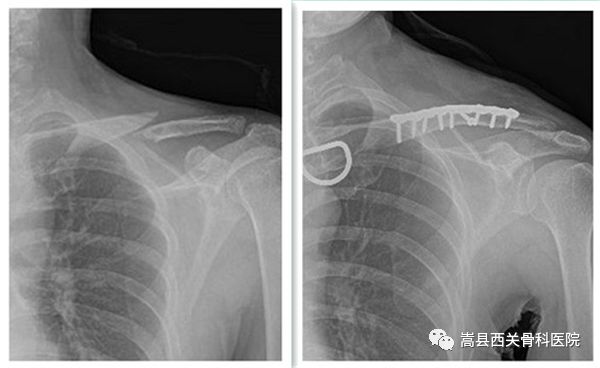

我院上肢创伤科部分患者术前术后对比图